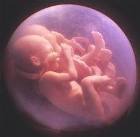

Врачи Израиля смогли успешно разделить в утробе матери близнецов, имеющих одну на двоих систему кровеносного снабжения, и тем самым сохранить детям жизнь.

Врачи Израиля смогли успешно разделить в утробе матери близнецов, имеющих одну на двоих систему кровеносного снабжения, и тем самым сохранить детям жизнь.

Когда у матери был срок беременности 20 недель, врачи заметили, что у близнецов одна плацента на двоих, а значит, общая кровеносная система. Тогда и было принято решение разделить плаценту при помощи новейших технологий. Теперь здоровью малышей, со слов врачей, ничто не может угрожать.

Два близнеца разделены в утробе матери

Когда у матери был срок беременности 20 недель, врачи заметили, что у близнецов одна плацента на двоих, а значит, общая кровеносная система. Тогда и было принято решение разделить плаценту при помощи новейших технологий. Теперь здоровью малышей, со слов врачей, ничто не может угрожать.